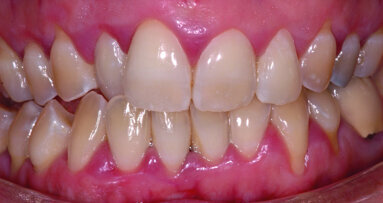

Bien que les restaurations adhésives présentent de nombreux avantages, elles ne sont pas toujours adaptées à toutes les situations cliniques. Il est essentiel de distinguer les cas où une préparation adhésive est préférable de ceux où les méthodes traditionnelles de rétention mécanique restent plus appropriées. Les restaurations collées sont idéales pour les patients avec des dents présentant des structures suffisamment solides, pour bénéficier d’une liaison chimique sans compromettre la résistance (Fig. 5). Cependant, dans des cas de perte de structure dentaire importante, ou lorsque la zone de restauration est trop étendue, une couronne complète avec une préparation traditionnelle pourrait être plus indiquée.

La sélection du type de restauration dépend aussi de facteurs tels que l’occlusion du patient, le type de dents (molaires ou prémolaires), et la situation clinique spécifique. Les critères de choix doivent donc prendre en compte à la fois les avantages des techniques adhésives et les limites potentielles liées à la complexité des cas.